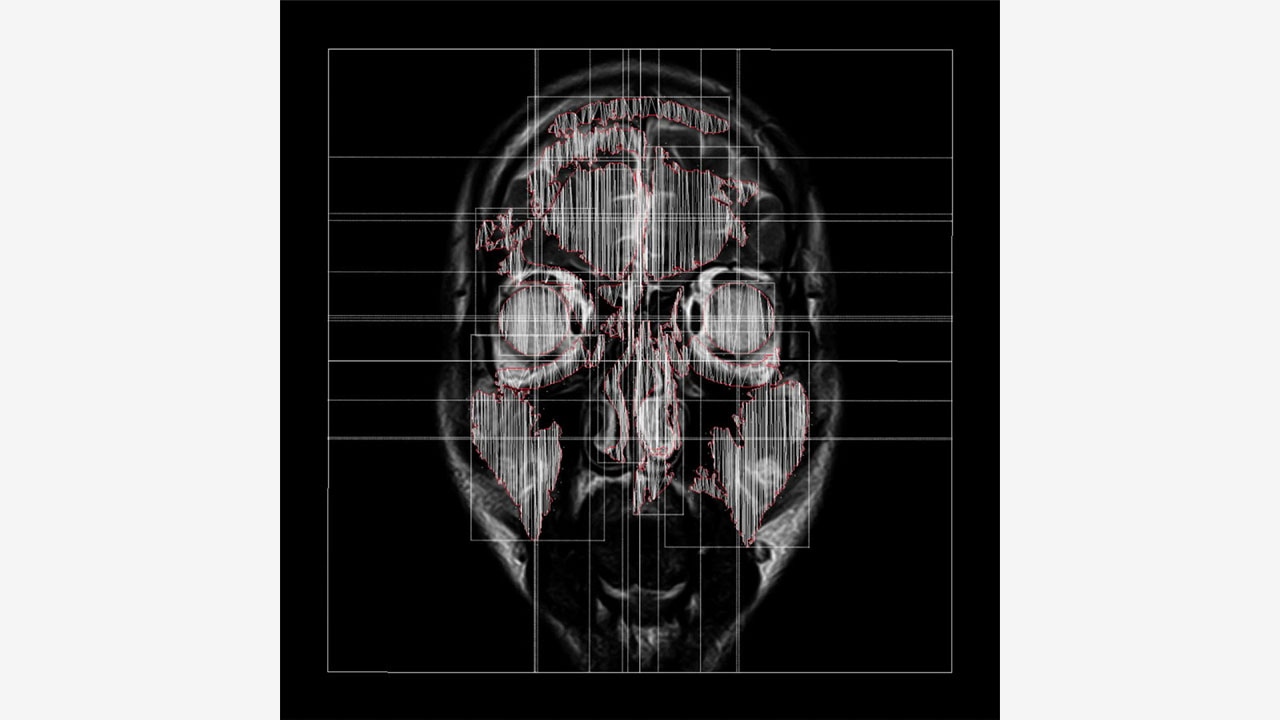

Visual using MRI sequence data(430 images) of my own brain got by myself at a medical facility(Date: 20 Jan 2021, Location: 35.672232571280645, 139.73366743753462).

I think that this NFT emphasizes the presence, existence and embodiment of human beings that cannot be duplicated and creates the concept of ma- terial intangibility and the situation that embodiment is not removed.